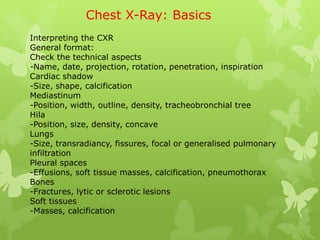

More Related Content Similar to Chest x ray basics Similar to Chest x ray basics (20) 1. Chest X-Ray: Basics

Interpreting the CXR

General format:

Check the technical aspects

-Name, date, projection, rotation, penetration, inspiration

Cardiac shadow

-Size, shape, calcification

Mediastinum

-Position, width, outline, density, tracheobronchial tree

Hila

-Position, size, density, concave

Lungs

-Size, transradiancy, fissures, focal or generalised pulmonary

infiltration

Pleural spaces

-Effusions, soft tissue masses, calcification, pneumothorax

Bones

-Fractures, lytic or sclerotic lesions

Soft tissues

-Masses, calcification